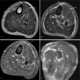

Rhabdomyolysis is a condition in which damaged skeletal muscle breaks down rapidly. Symptoms may include muscle pains, weakness, vomiting, and confusion. [Source: Wikipedia ]